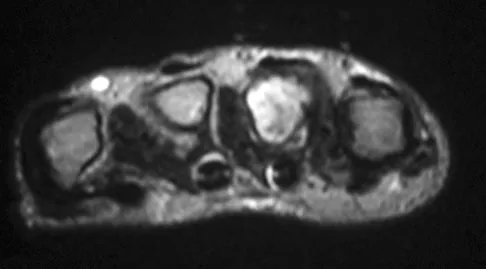

A 19-year-old girl has had pain and swelling in the right ankle for the past 4 months. She denies any history of trauma. Examination reveals a small soft-tissue mass over the anterior aspect of the ankle and slight pain with range of motion of the ankle joint. The examination is otherwise unremarkable. A radiograph and MRI scan are shown in Figures 45a and 45b, and biopsy specimens are shown in Figures 45c and 45d. What is the most likely diagnosis?